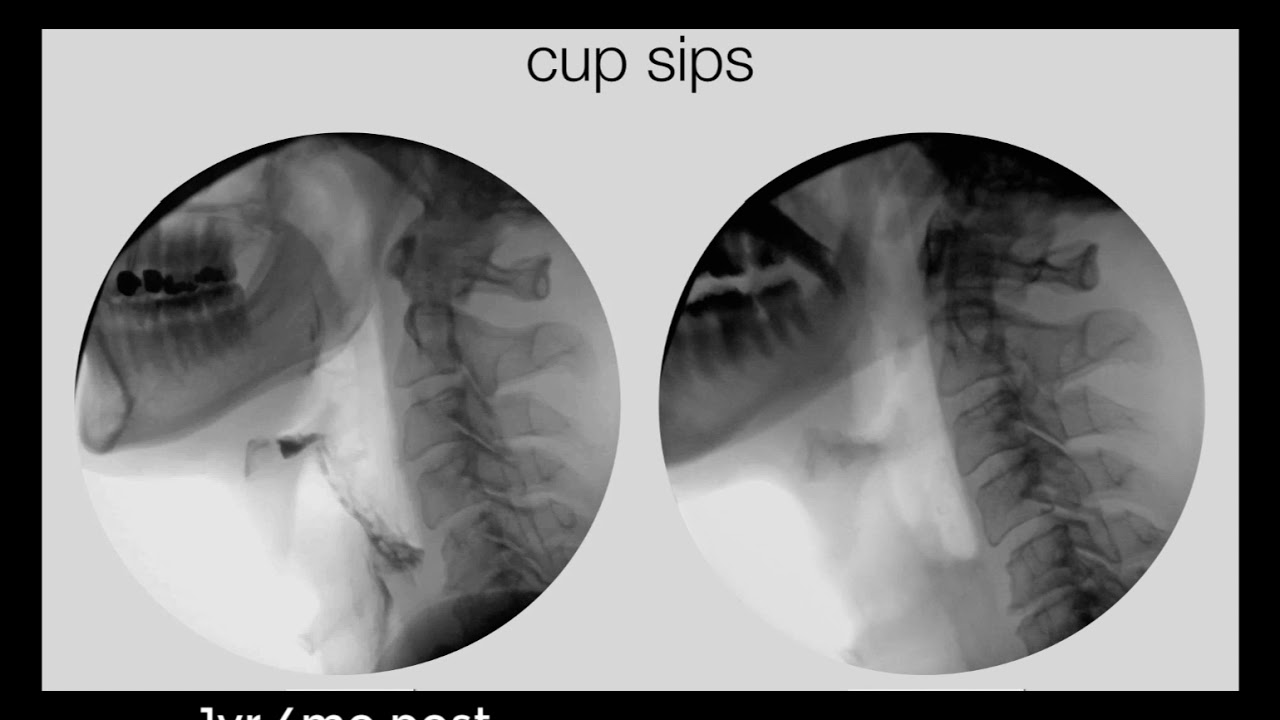

• The Swallowing Physiology Series Oral Preparation Down The Hatch The Swallowing Podcast Lyssna Har Poddtoppen Se

• Swallowing Physiology Series Laryngeal Vestibule Closure Down The Hatch The Swallowing Podcast Lyssna Har Poddtoppen Se